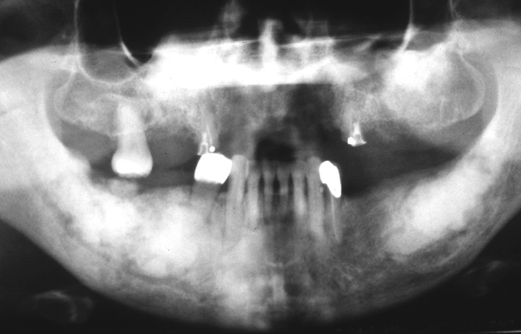

gardner syndrome